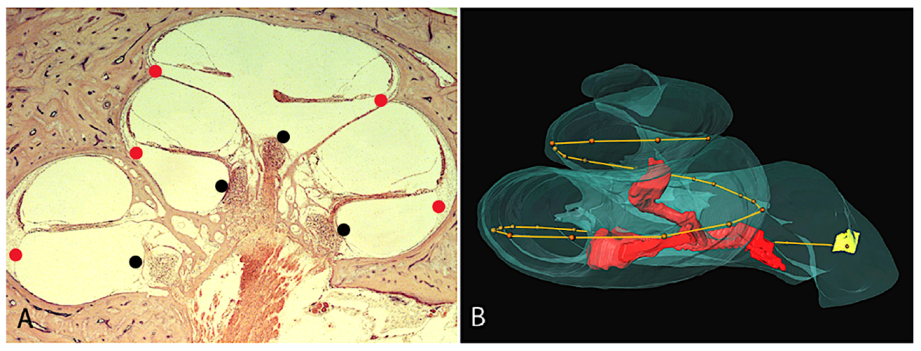

2.1. Angular Measurements of the Human Cochlea in CI Patients Using 3-Dimensional Reconstruction

- Danielian, A.; Ishiyama, G.; Lopez, I.A.; Ishiyama, A. Morphometric linear and angular measurements of the human cochlea in implant patients using 3-dimensional reconstruction. Hear Res. 2020, 386, 107874. [Google Scholar] [CrossRef] [PubMed]

| Danielian et al. [2] | 15 | 3D reconstruction from H&E 20 µm light microscopy | 1.9 to 1.95 X = 695° | 14.44–16.97 mm X = 15.9 mm | 16.34–18.92 mm X = 17.9 mm | 31.38 –36.44 mm X = 34.5 mm | 876°–1052° X = 947° 35.4–43.6 mm | 34–46% length X = 40% 65–80% Angular X = 74% |